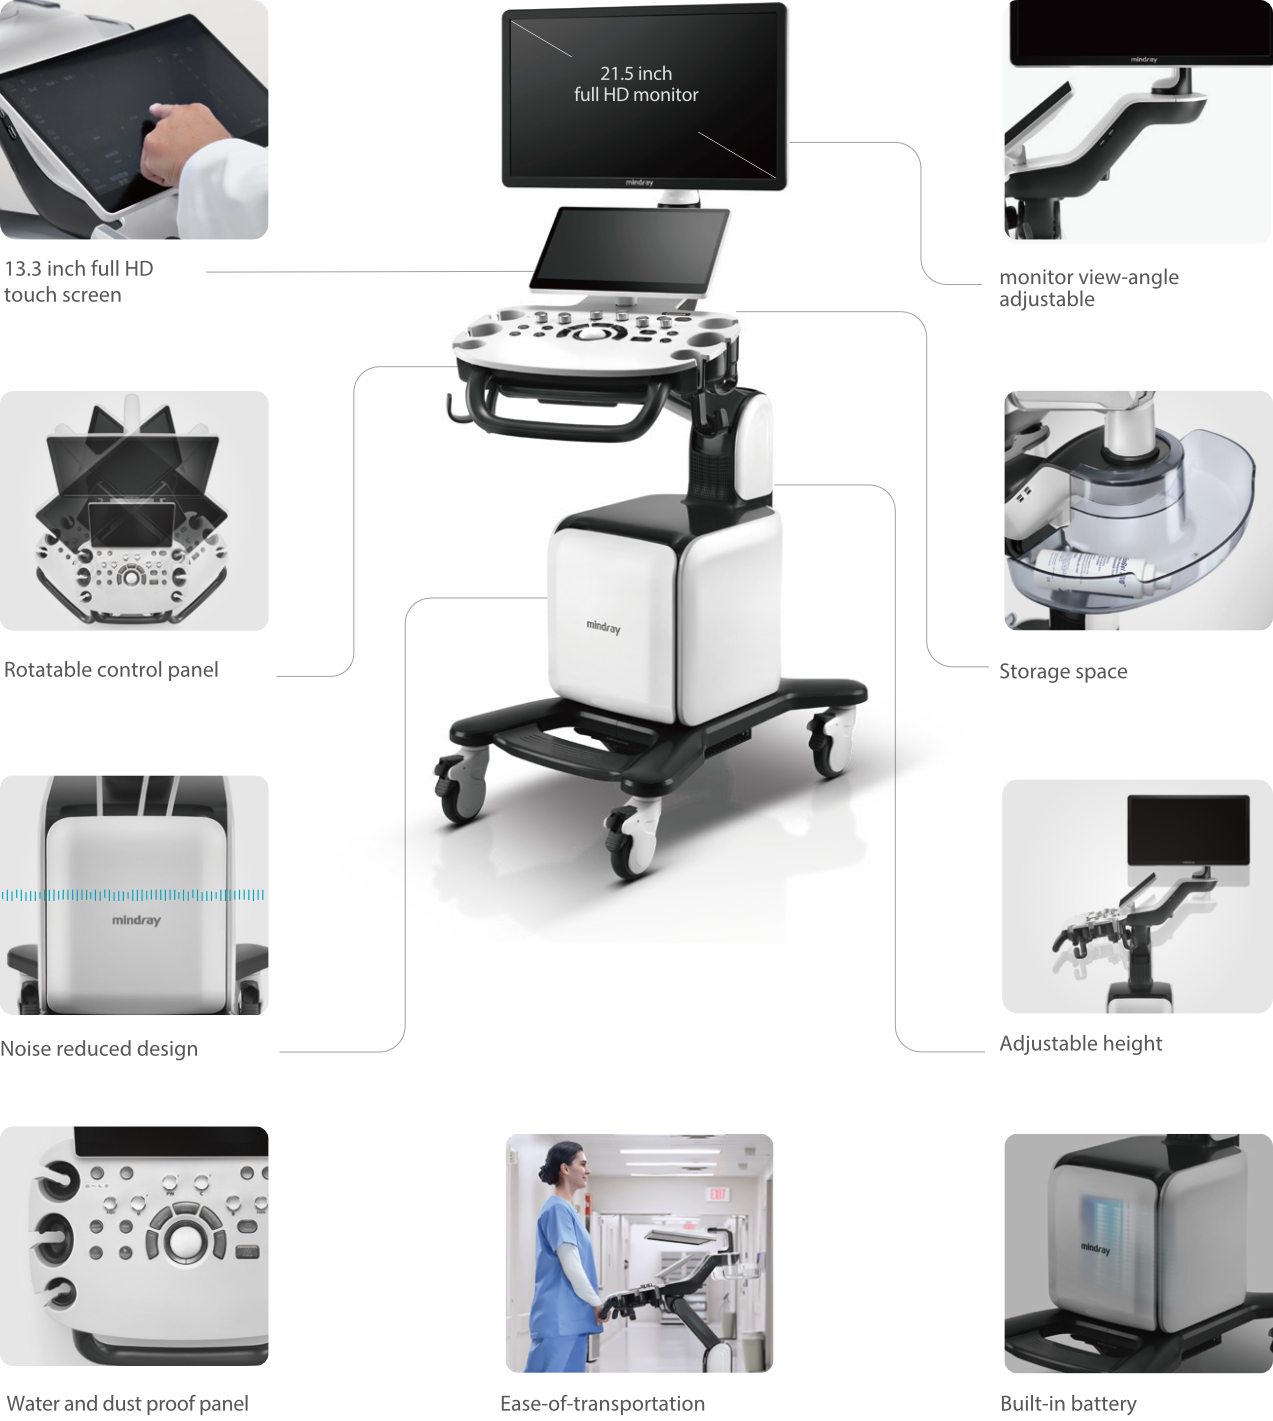

Nuewa i8

El Nuewa I8, ofrece una claridad de imagen inigualable, elevando tu confianza y eficiencia a nuevas alturas. Diseñado con el máximo cuidado, minimiza la fatiga y maximiza la conveniencia a lo largo del proceso de operación.

Impulsado por la innovadora plataforma ZST + y un conjunto completo de soluciones inteligentes, el Nuewa I8 ofrece una claridad de imagen inigualable, impulsando tu confianza y eficiencia a nuevas cotas. Diseñado con la máxima atención al detalle, minimiza la fatiga y maximiza la comodidad durante todo el proceso quirúrgico.